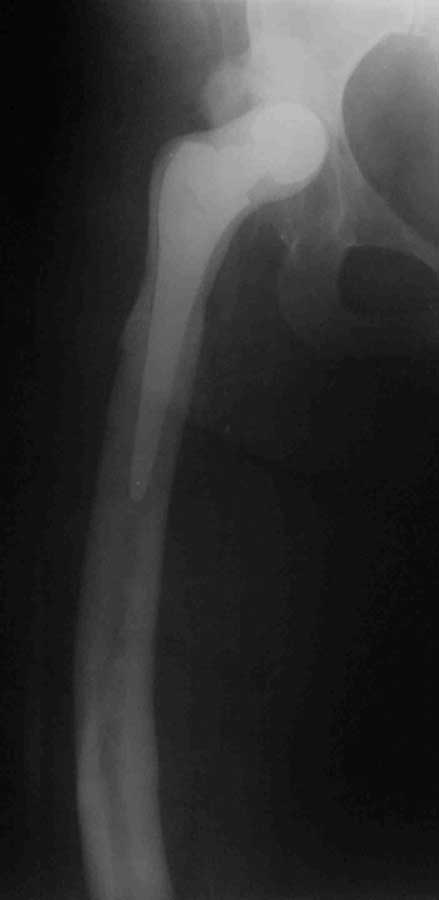

Уважаемые коллеги, к нам поступила женщина 45 лет с такой вот ситуацией: Операция около 1,5 месяцев назад: тотальное б/ц эндопротезирование с остеотомией проксимального отдела бедра. Послеоперационный период - без особенностей, рана зажила первично, выписана домой. В анамнезе в детском и юношеском возрасте несколько оперативных вмешательств на вертлужной впадине и бедре по поводу врожденного вывиха бедра, судя по рубцам, протекавшие не совсем гладко. около 2,5 недель назад пациентка начала отмечать вечерние подъемы температуры до 38. примерно в это же время выявлен высокий тромбоз поверхностной бедренной и общей бедренной вен, несмотря на прием антикоагулянтов. Пунктирован сустав - получен рост золотистого стафилококка. Учитывая острый тромбоз, назначена супрессивная а/б терапия с учетом чувствительности. В настоящее время: тромбоз с положительной динамикой с признаками реканализации, небольшой лейкоцитоз, СРБ до 12, вечерние свечки до 38 (не каждый день), субъективно - чувствует себя лучше. Локально: плотный отек в области п/о рубца, гиперэмия, небольшое количество пузырей с серозным отделяемым (сожалею, сегодня не успел сфотографировать). Вопросы: -какова вероятность локализации процесса в мягких тканях или не стоит выдавать желаемое за действительное? - объем ревизионного вмешательства: сохранять эндопротез или нет? одноэтапно или двухэтапно? На фоне остеотомии бедра испльзовать цементный спейсер или поробовать импакционную пластику с добавлением антибиотика или пластику - дистально, цемент проксимально?

2. Бедренный компонент не выглядит стабильным, и стабильным на протезе с прокимальной фиксацией быть не может. Антиротационная пластинка слегка удерживает дистальный отломок, а плоскость остеотомии сложно назвать хорошо адаптированной. Из чего следует - бедренный компонент удалять. Вертлужный, если стабилен, можно оставить с заменой вкладыша

2.а какие признаки нестабильности его есть? Явной нестабильности точно нет, вероятной - под большим сомнением (снимки разной жесткости), антиротационная пластина никоим образом не удерживает дистальный отломок, в случае нестабильности она уже 10 раз сломалась бы.

Интраоперационно - все было очень стабильно, пластина была прикручена "на всякий случай" по рек-ям зарубежных коллег. Почему ножка тип цваймюллер стала проксимальной фиксации? Часть народа говорит, что при ее использовании пластина вообще не нужна.

Не знаю как другие, но по выложенным рентгенограммах можно заподозрить лизис вдоль медиальной стенки дистального фрагмента. То что проксимальный фрагмент стабилен сомнений нет, по поводу дистального - как то сомнительно.

Конечно, гадать на таком рентгене - стабильны компоненты или нет - все равно что на кофейной гуще, можно сделать рентген в двух проекциях и без ротации ножки. Но точно определить можно лишь на ревизии. Будешь убирать или нет, спейсер или пластика или что-то еще(кто-то писал о вакуумном ведении протезной раны в течении недели после ревизии и дебридмента) - дело другое, но ревизовать надо. чем раньше тем лучше.

Фрагменты можно называть хорошо адаптироваными, но не менее хорошо видно диастаз между ними как минимум 3-4 мм на послеоперационном и последующем снимке.

Нельзя назвать абсолютно стабильной фиксацию дистального конца бедра, поскольку ножка слишком коротка. Вагнер был предпочтителен изначально. И антиротационный компонент там присутствует в виде ребер. Пластина, тем более такая короткая, пользы не приносит. Конечно и бактериальный компонент никто не отменял, но изначальная нестабильность сыграла пагубную роль.